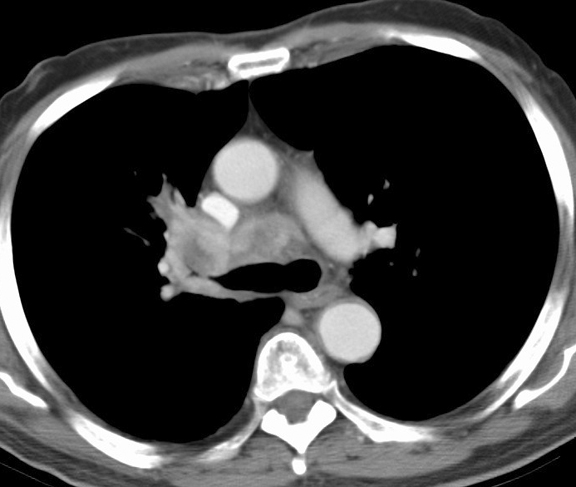

RUL Collapse Case 1 CT(b)